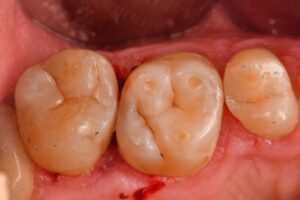

October 13, 2025 Direct Restoration #ClamplessDME #GarrisonCompositight #MajestyES2Universal Previous Post Next Post